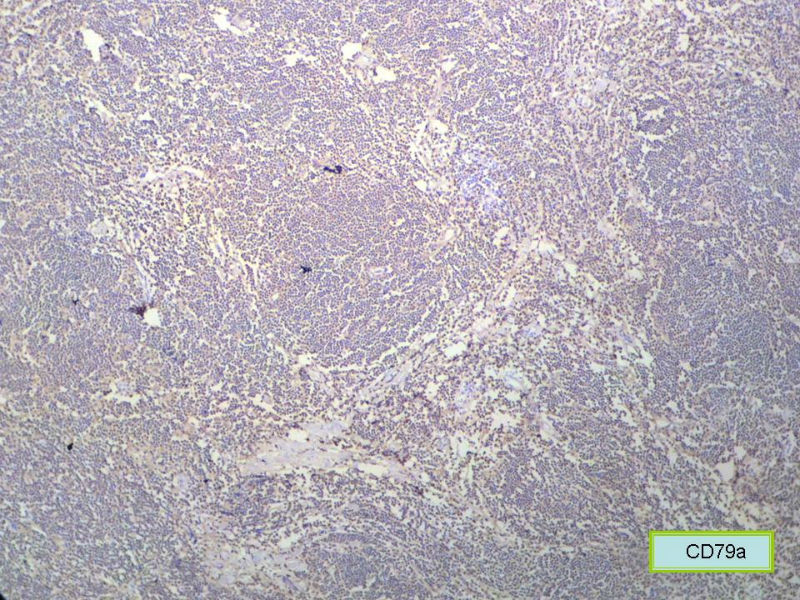

请再标记CD20和CD79a!图片中阳性不明确,根据T细胞标记看,应该是B细胞结节。Ki67散而少,不支持低级别滤泡性淋巴瘤,若B细胞弥漫阳性,则是惰性B细胞非霍奇金淋巴瘤,首先考虑套细胞,然后是边缘区淋巴瘤。不做生发中心标记,Bcl-2在小B细胞淋巴瘤分类中无意义。

赞成以上专家的讨论,根绝病史,HE形态考虑小细胞病变,CD3、CD5散在+,还是倾向淋巴造血系统病变,CD20、CD79a阳性不明确,可以考虑复查,加做PAX-5,核阳性容易判断,另再加做鉴别其它小细胞肿瘤的抗体:CD99、CD43、CyclinD1、CK、CgA、Syn等,了解病史:骨髓、末梢血、肝、脾等。

CD20(+),Kappa(+),ki-67(+)>2%,Lambda(+),Pax-5(+),符合粘膜相关淋巴瘤。

本例是发生在特殊部位“结膜下”,HE肿瘤细胞形态形态一致,形似单核样B细胞。B细胞标记若明确阳性,诊断MALT是挺合理的。